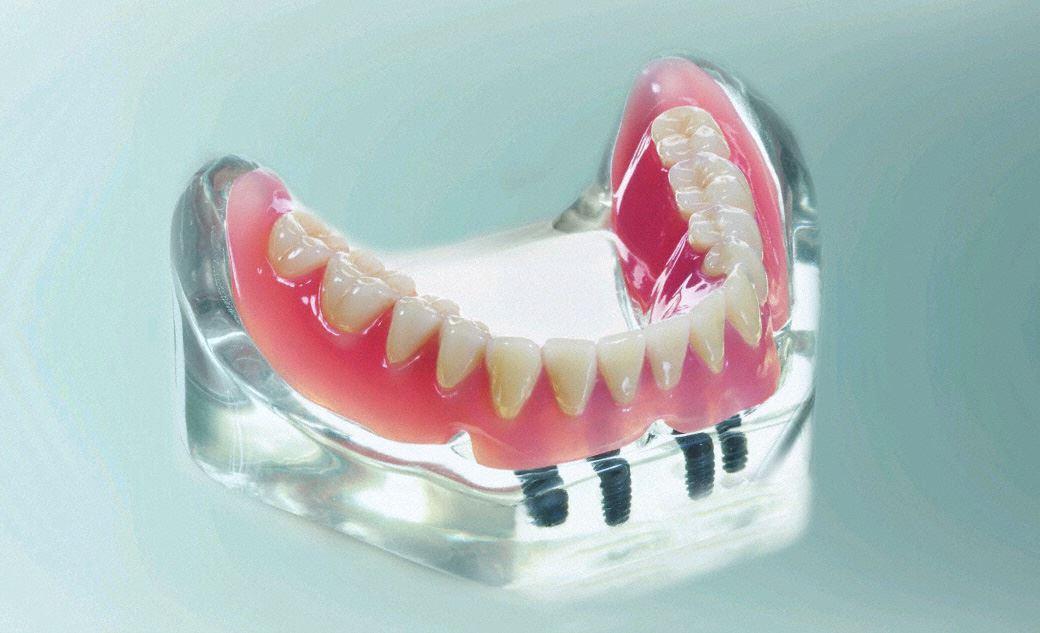

Verankerungen für herausnehmbaren Zahnersatz

Besonders im Unterkiefer ist der Halt einer totalen Prothese problematisch. Oftmals werden Sprache und Kauen durch den problematischen Sitz stark beeinträchtigt. Zwei bis vier Implantate geben dem totalen Zahnersatz guten Halt.